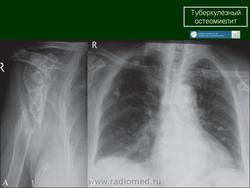

Туберкулез плечевого сустава (омартрит)

Встречается это заболевание сравнительно редко, на его долю приходится от 0,8 до 4% общего числа костно-суставных поражений при туберкулезе (А. В. Судакевич). Это заболевание возникает преимущественно в возрасте 15—25 лет и в третьем, четвертом десятилетиях жизни. Наиболее ранним симптомом при поражении плечевого сустава является слабость в руке. Более выраженные клинические симптомы в виде болей, атрофии мышц (в первую очередь дельтовидной), ограничение движений появляются при переходе процесса на сустав. При рентгенологическом исследовании туберкулезные оститы обнаруживаются редко, что связано с малосимптомным клиническим течением. Оститы обычно обнаруживаются вблизи межбугорковой борозды, в большом бугорке, располагаются чаще в губчатом веществе, реже — под корковым слоем. Однако первичные очаги могут располагаться и в анатомической шейке плечевой кости. В этом случае процесс распространяется в сторону от сустава на метафиз и диафиз с разрушением коркового слоя и вовлечением в процесс мягких тканей. Периостальная реакция в этих случаях отсутствует. Однако при образовании свищей и присоединении вторичной инфекции может иметь место. Значительно реже первичные очаги встречаются в области лопатки. При переходе процесса на сустав нарастает остеопороз, иногда по типу пегого. Контуры суставных поверхностей становятся смазанными, суставная щель суживается. Появляются краевые очаги деструкции костной ткани как в головке плечевой кости, так и в суставной поверхности лопатки с нечеткими контурами. Иногда выявляются губчатые секвестры, которые кажутся более плотными на фоне остеопоротичной окружающей костной ткани. Иногда туберкулезное поражение плечевого сустава протекает по типу сухой костоеды. Г. И. Турнер (1937) в развитии сухой костоеды особое значение придает невриту подкрыльцового нерва. Для этой формы характерно отсутствие эксудации и обильного гнойного выпота, медленное упорное течение, рубцовое сморщивание суставной капсулы. При рентгенологическом исследовании в этих случаях остеопороз мало выражен. В наружном отделе эпифиза плечевой кости обнаруживается краевая узура овальной формы с достаточно четкими контурами и более или менее выраженным ободком склероза. Расширение краевого дефекта может происходить в обе стороны от межбугорковой борозды, в сторону головки и большого бугорка. Суставная щель несколько сужена. Атрофия и укорочение кости могут быть значительными, однако патологических вывихов не наблюдается. Туберкулезный артрит плечевого сустава отличается длительным хроническим течением, в результате которого разрушению могут подвергаться головка плечевой кости и суставная впадина лопатки. Затихание процесса характеризуется уменьшением и исчезновением признаков воспаления. При рентгенологическом исследовании можно заметить уменьшение остеопороза, четкость контуров очагов деструкции и суставных концов костей. Постартритическая фаза характеризуется значительными анатомическими разрушениями, присоединившимися дистрофическими изменениями по типу остеоартрозов и склонностью к рецидивам. Туберкулезное поражение плечевого сустава приходится дифференцировать с остеоартропатией при сирингомиелии. Необходимо учитывать медленное постепенное нарастание клинических проявлений при сирингомиелии, возможное увеличение объема и разболтанность сустава, поражение нескольких суставов, нарушение чувствительности. При рентгенологическом исследовании выявляется рассасывание значительной части эпифиза плечевой кости, наличие поперечных переломов, плотных, причудливой формы напластований вокруг плечевой кости